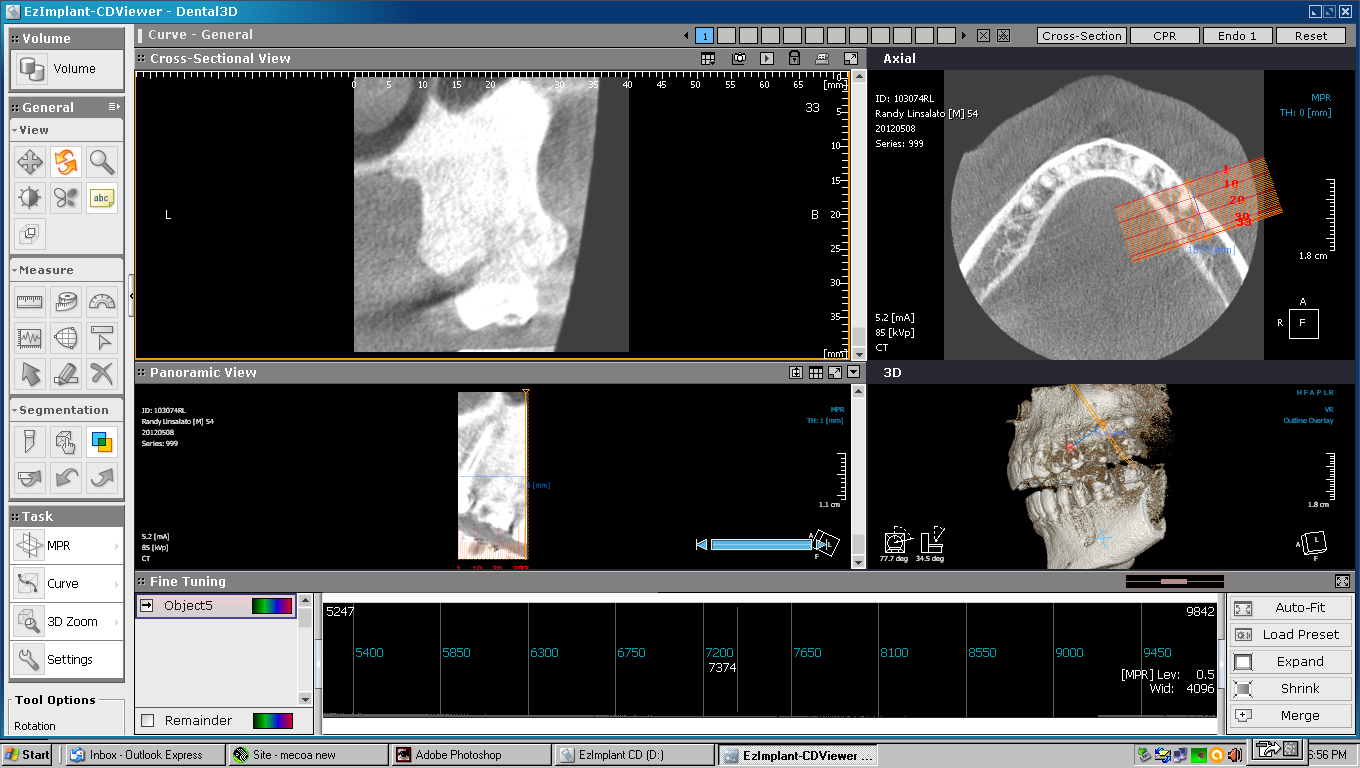

He took the scan below to see the extent of the Osteoma.

As you can see the dense bone mass extends from my lower sinus down around the roots my teeth 14 and 15

Involvement of teeth 13,14, and 15 is obvious.